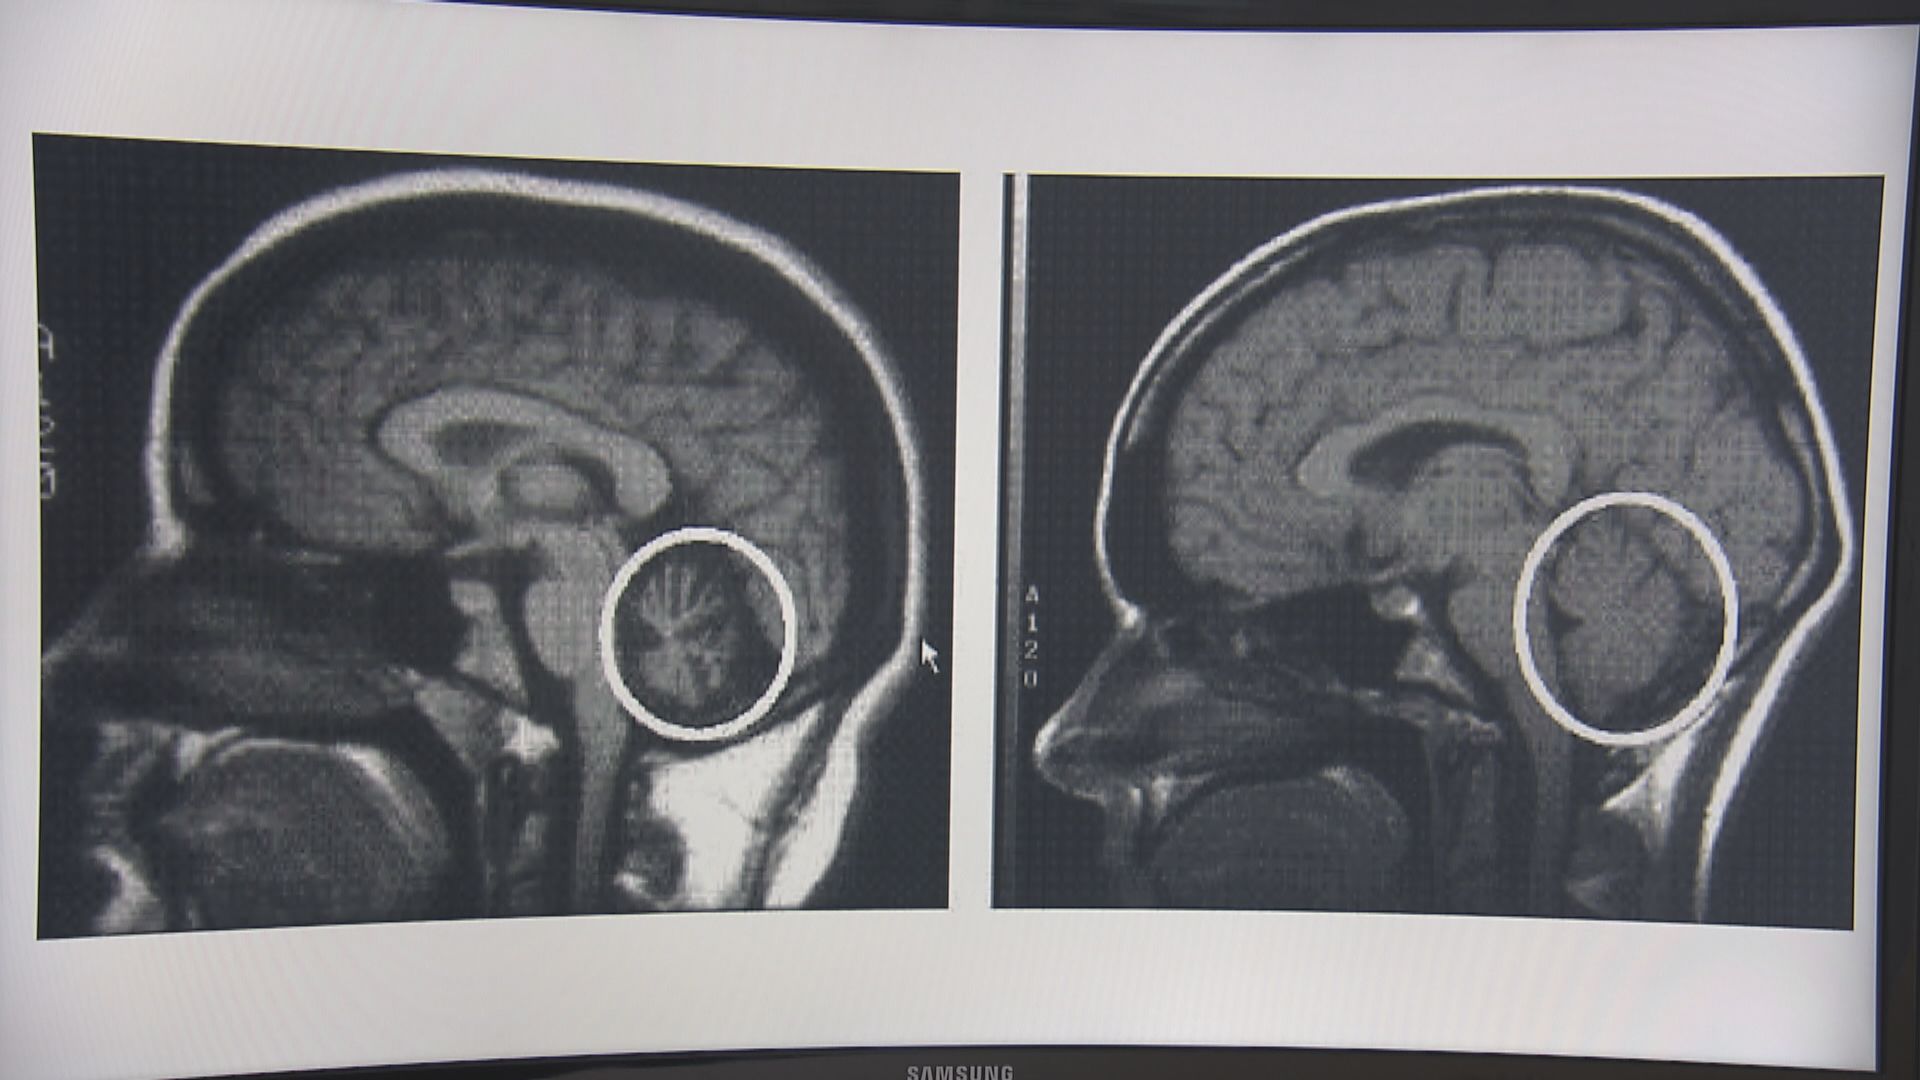

【Now新聞台】有些人的眼睛會無端腫起,大大影響外觀之餘,甚至連視力都都漸漸退化,原來有可能是眼睛周邊的血管出現病變。到底為甚麼會這樣?醫生又會用甚麼方法處理?今集《杏林在線》會為大家講解。